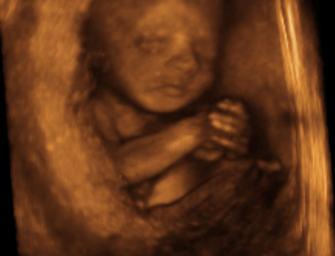

sonogram at 26 weeks

baby aborted around this time